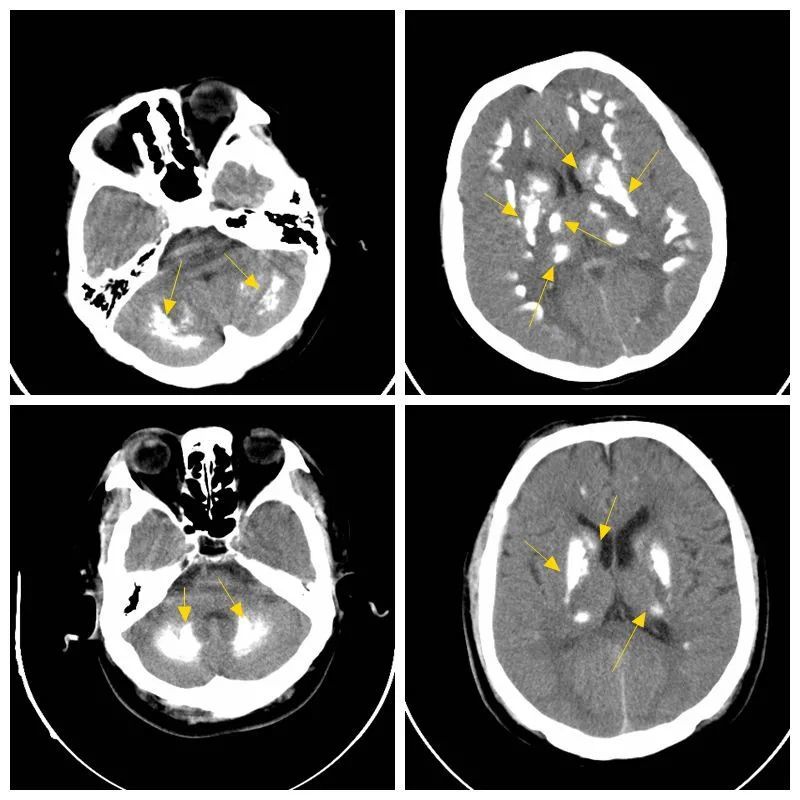

核形钙化:钙化与尾状核,豆状核,丘脑,小脑齿状核形态一致.

豆状核,尾状核,丘脑及双侧灰白质交界带对称性斑片状,条状高密度钙化

6 fahr 病(双侧苍白球-纹状体-齿状核钙化) fahr 病目前病因不详,主要